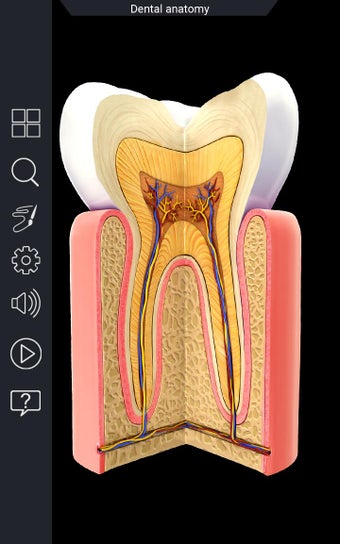

Uygulama, diş hekimliği ve anatomisi öğrencileri ve öğretmenleri için olmazsa olmaz bir araçtır. Hem öğrenciler hem de öğretmenler için bir eğitim aracı olarak kullanılabilir. İnsan dişlerini yüksek kaliteli grafiklerle keşfetmenizi sağlar. Ayrıca insan dişlerine derinlemesine bir bakış sunar.

Uygulama, her bir parçayı seçerek adını görüntülemenize veya ilgili bilgileri okumanıza olanak tanır. Her bir parçayı gizlemeyi veya göstermeyi seçebilirsiniz. Ayrıca 360° döndürebilir veya yakınlaştırıp uzaklaştırabilirsiniz. Kamerayı modelin farklı bir görünümünü elde etmek için hareket ettirebilirsiniz.